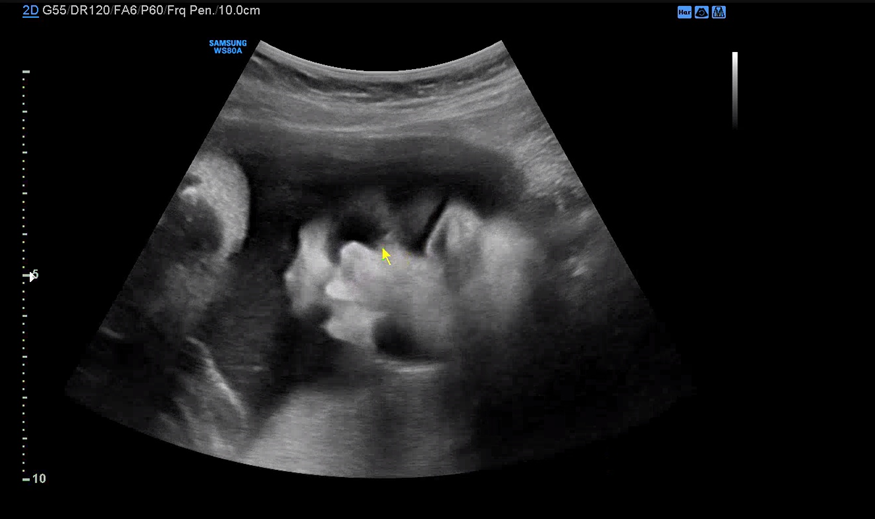

막달 검사를 마치고 30분 정도 대기한 뒤 원장을 진료를 봤다. 4분가량 배 초음파로 아기의 상태를 체크해주시는데 BPD, Fetal HR, AC, FL 순서로 봐주시고 마지막으로 아기 얼굴을 보여주셨다.

자면서도 입은 오물오물.